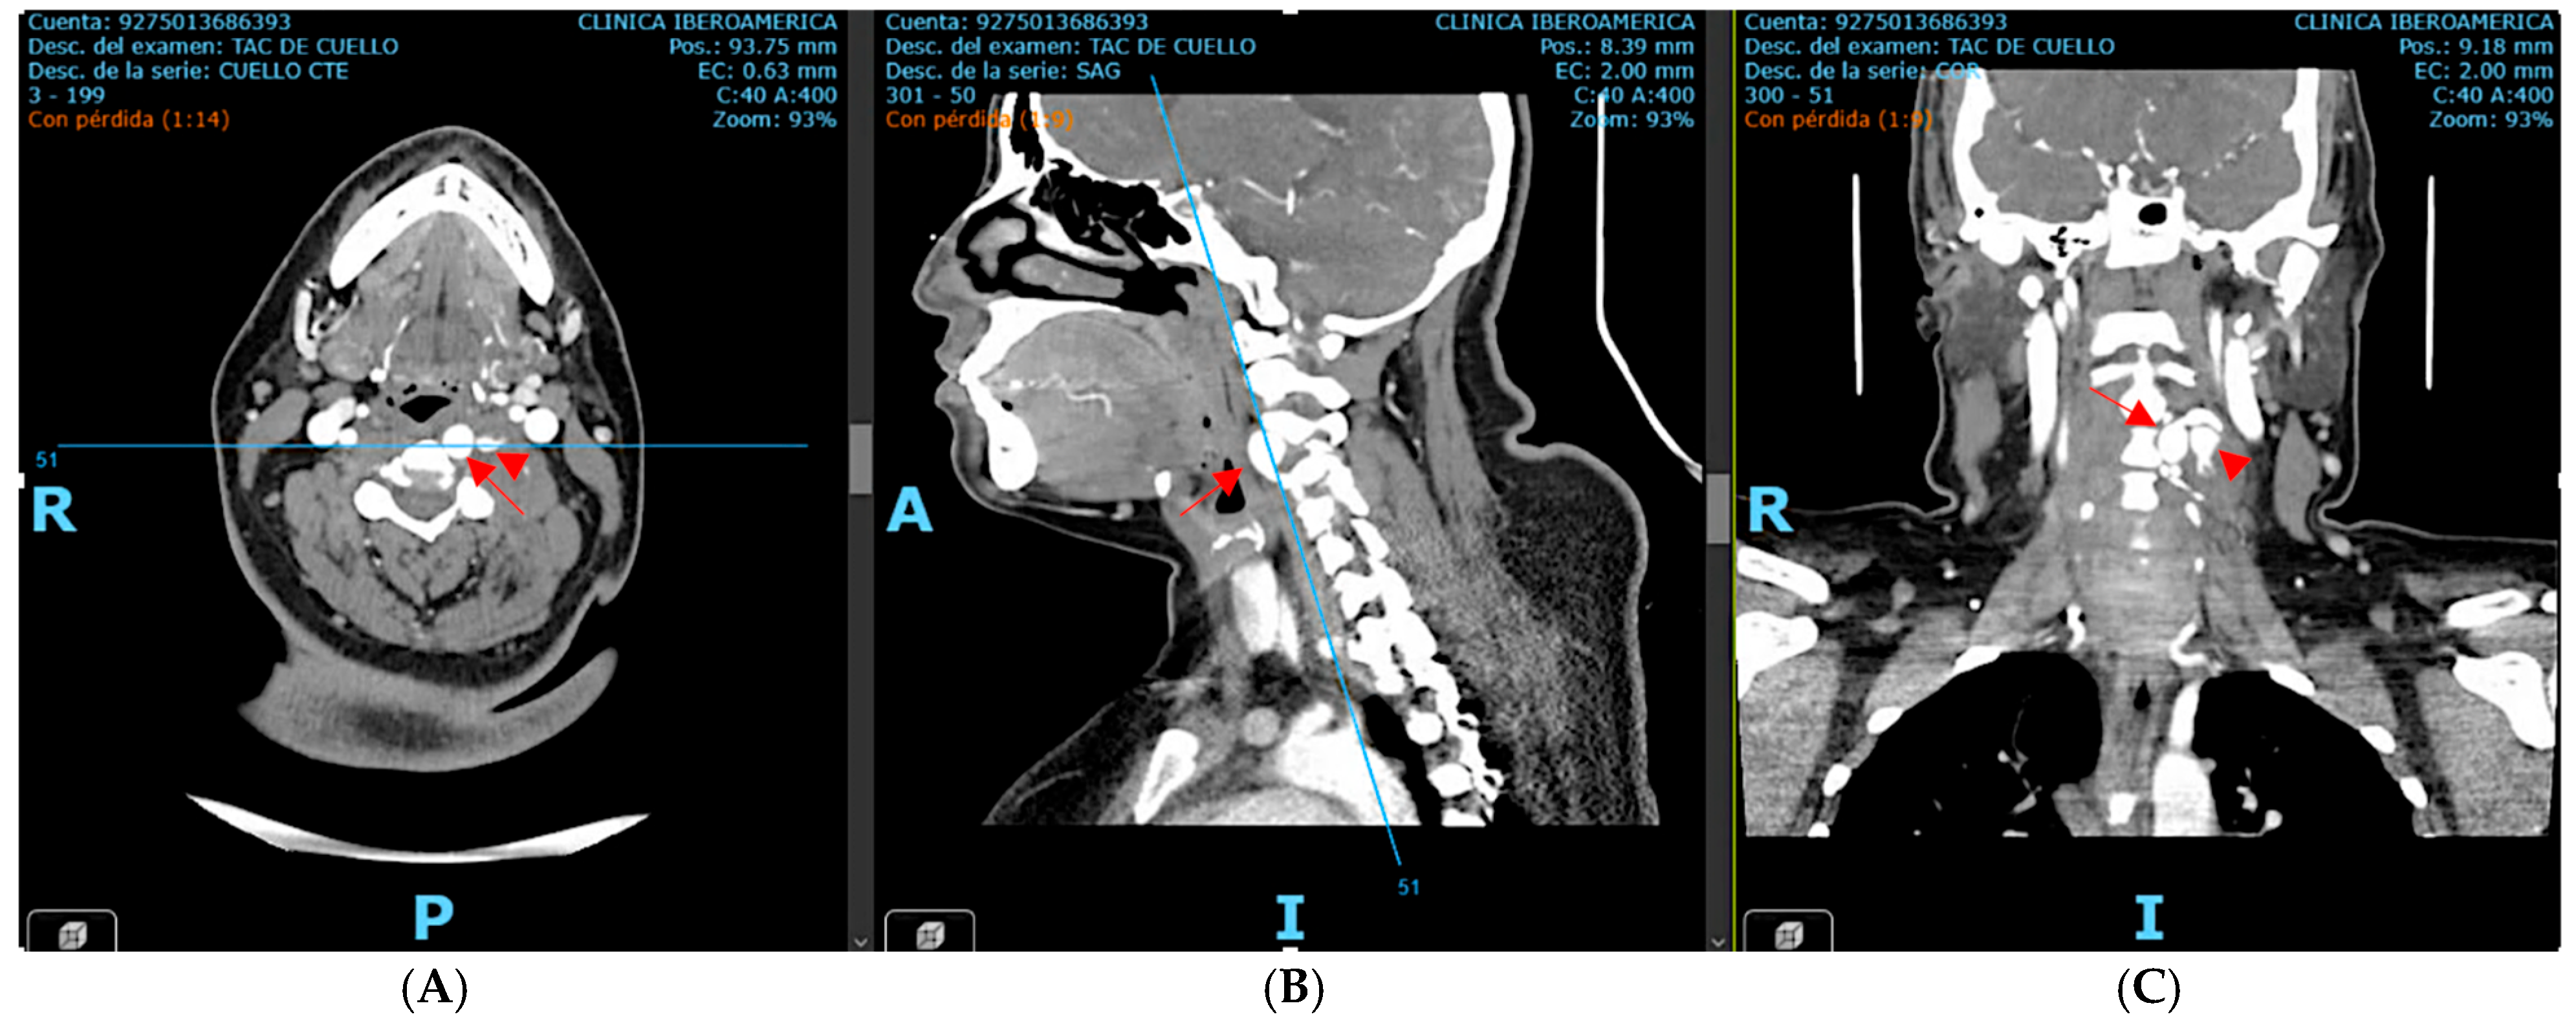

The case was urgently discussed in a multidisciplinary neurovascular team meeting comprising radiologists, interventional neurosurgeons, and neurologists. After a detailed discussion with the patient regarding the risks and benefits of available therapies, it was decided, considering the time of evolution, the patient’s age, and the aneurysm’s characteristics, to perform a reconstructive endovascular treatment using a flow-diverting stent (Pipeline Shield) (Micro Therapeutics Inc., Irvine, CA, USA) (Figure 4), initiating dual antiplatelet therapy (clopidogrel 75 mg plus acetylsalicylic acid 100 mg starting 5 days prior to the procedure and continued for 90 days). The procedure was performed using a triaxial system: a 5 Fr Navien catheter was advanced with the aid of a 0.035 guidewire. Through this, a Phenom 27 microcatheter (Medtronic, Minneapolis, MN, USA) and a 0.014 Synchro microwire (Stryker Neurovascular, Fremont, CA, USA) were navigated across the aneurysmal sac with subtle maneuvers under continuous fluoroscopic and roadmapping guidance. The distal tip of the microcatheter was successfully positioned in the left V3 segment. After systemic intravenous heparinization, the microwire was withdrawn, and a single Pipeline Shield flow-diverting and artery-remodeling stent (4.5 × 35 mm) was advanced and deployed, achieving a healthy-to-healthy proximal artery reconstruction and completely covering the aneurysm neck, which initiated its occlusion process. Control angiograms demonstrated adequate stent apposition, maintained parent vessel patency, and no periprocedural complications. Femoral access was closed with an 8 Fr Angio-Seal device (Terumo Medical Corporation, Somerset, NJ, USA). Post-procedural imaging follow-up with digital subtraction angiography (DSA) confirmed stent positioning and vessel patency.

Figure 4. Post-procedural digital subtraction angiography (DSA) and three-dimensional reconstruction images following reconstructive endovascular treatment with a flow-diverting stent (Pipeline Shield). The stent is clearly visualized along the course of the left vertebral artery and is indicated by the red arrow. Source: patient’s medical record, published with prior authorization.